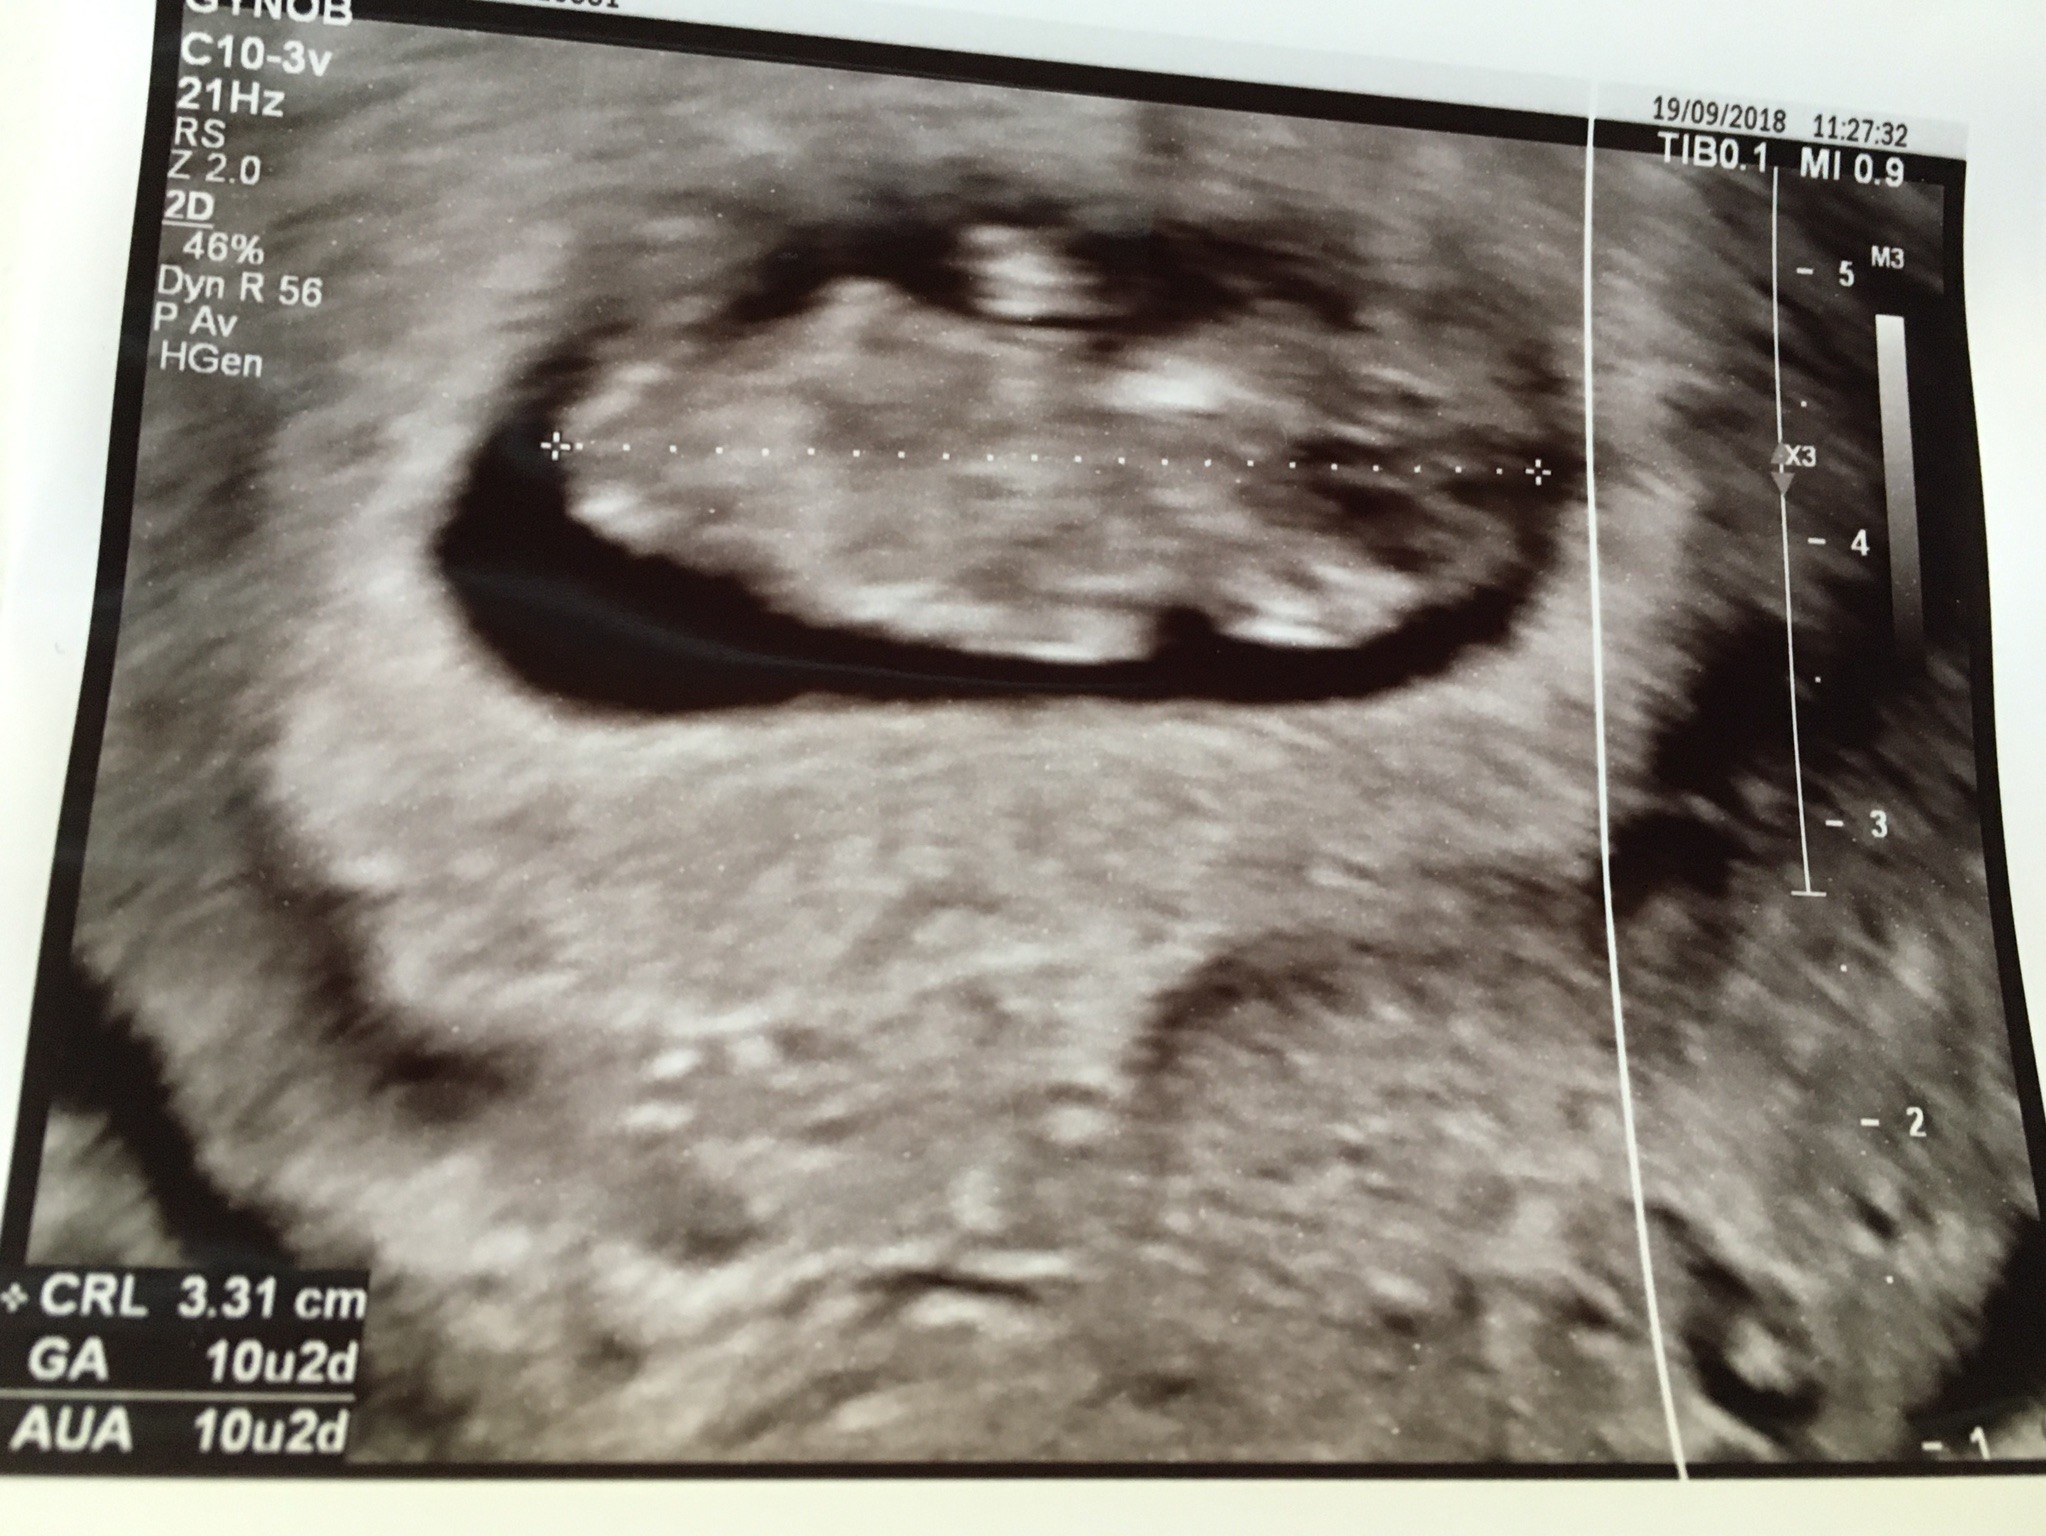

Usg miałam wykonane jeszcze dopochwowo , bo lepiej tak widać Maluszka. Jest CUDowny. Już się w nim (albo w niej) wszyscy zakochaliśmy. Maleństwo bardzo ruchliwe, widziałam rączki, nóżki, oczka..... przepiękny widok. Serduszko ślicznie bije (chociaż nie słuchałyśmy go dzisiaj). Wg OM dzisiaj jest 11+0 , wg usg 10+1, czyli już Maleństwo nadrobiło 1 dzień różnicy. Na nowo lekarka obliczyła mi termin porodu -18.04.2019 czyli Wielki Czwartek.... ale uspokoiła mnie, że w 19. tygodniu po usg oblicza się wszystko na nowo i ustala konkretną datę porodu. Dostałam już termin na to usg na 21.11.